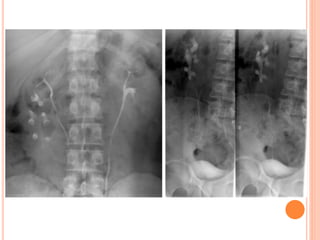

IVU

 Kidney film 3 min.

 A KUB radiograph is obtained to assess temporal

symmetry and opacification.

 Compression? (Contraindications ).

 Bladder film early

(suspected bladder

lesion).

 KUB after release of

compression( 15 min).

 delayed images for

bladder distention, and

oblique, prone, or post-

void images.

INTERPRETATION OF IVU

 Renal size.

 position of the kidney.

 Renal parenchyma at

nephrographic phase.

 Renal contour

(interpapillary line).

URETERS

- peristalsis.

- Stasis of contrast.

- Medial deviation.

- Lateral deviation.

- Anatomic narrowing.

- Ureter diameter (8mm).

- Filling defect.

 Medial deviation of the ureter should be considered

when the ureter overlies the ipsilateral lumbar

pedicle.

 lateral deviation should be considered when the

ureter lies more than 1.5 cm beyond the tip of the

transverse process.

BLADDER

- Bladder contour.

- Wall thickness and

irregularities.

- Extrinsic compression.

- Post-void ( residual

urine, upper tract

dilatation).